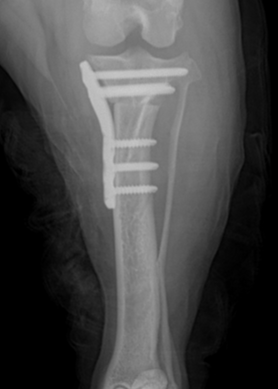

회전한 뼈가 움직이지 않도록 TPLO plate와 screws로 단단하게 고정해 뼈가 안정적으로 붙을 수 있게 합니다.

.png)

수술후 방사선 영상

수술 후 방사선 평가에서는 수술 전 TPA 30°였던 것이 수술 후 4.7°로 교정되어 목표 범위에 가깝고, tibia의 전반적인 정렬도 계획대로 양호하게 확인되었고 절골면이 서로 잘 맞닿아 있었고, 과도한 틈이나 어긋남 없이 양호한 접촉 상태였습니다.